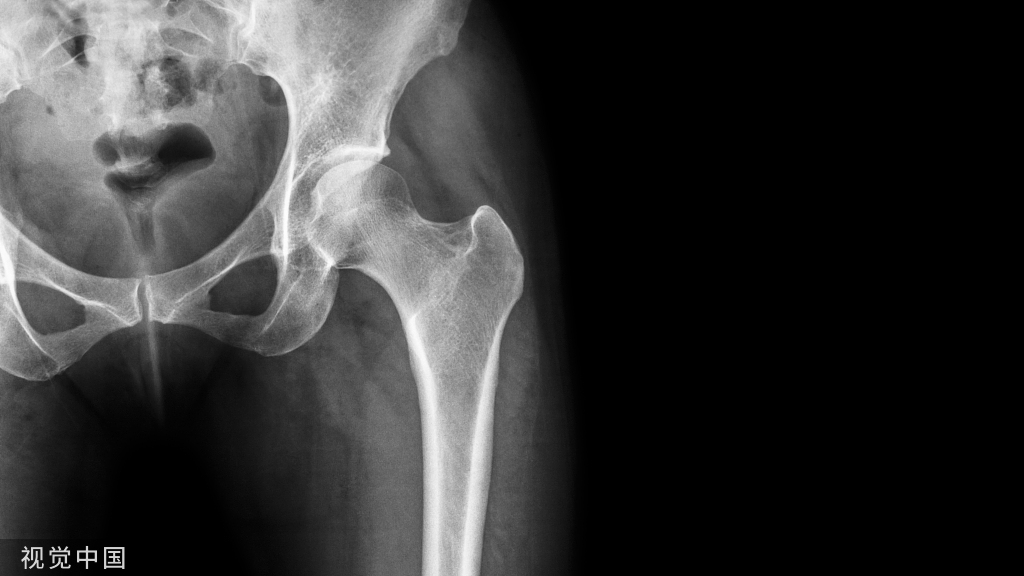

X线表现与测量

足的x线测量对于进一步了解拇外翻的病理及设计手术方案是非常重要。负重足的基本功能,很多足的畸形在负重状态下可以表现得更清楚。一些测量指标在负重和非负重状态下可以明显不同。足部各种x线测量一般都是在足负重位摄片下完成。手术前常规需要拍摄患足负重位、前后位和侧位,根据需要拍摄足的非负重位内旋斜位和籽骨轴位。

2:侧位片观察和测量第1跖骨倾斜角  第1跖骨中轴线和地面水平线的夹角。正常约为15°。此角对于术前选择手术方式意义不大,可以作为术后判断第1跖骨位置的一个参考。

第1跖骨相对于距骨关系  比较距骨颈中轴线和第1跖骨中轴线的关系。正常两线应当重叠。跖骨线位于距骨线背侧时,表示跖骨头背伸。跖骨线位于距骨线跖侧时,表示跖骨头跖屈。

第1、2跖骨关系  分别画出第1、2跖骨干背侧缘,比较两者之间的关系。正常时,两重叠或平行。在第1跖骨头背伸或跖屈时,可见两者成角。